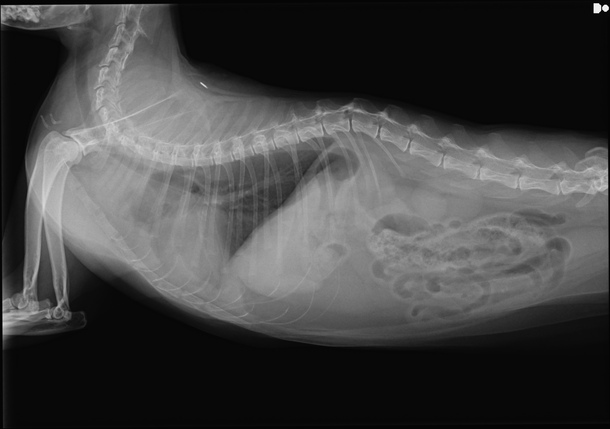

腫瘍と胸水が確認されました

血液検査は、抗がん剤治療が行えるギリギリの範囲ということで、予定通り投与を行いましたが、レントゲンを撮ったところ、これまで縮小していた腫瘍が、再び、大きくなってきていました。

さらに、胸水が溜まってきており、数日、特に注意して様子を見てくださいとのことでした。